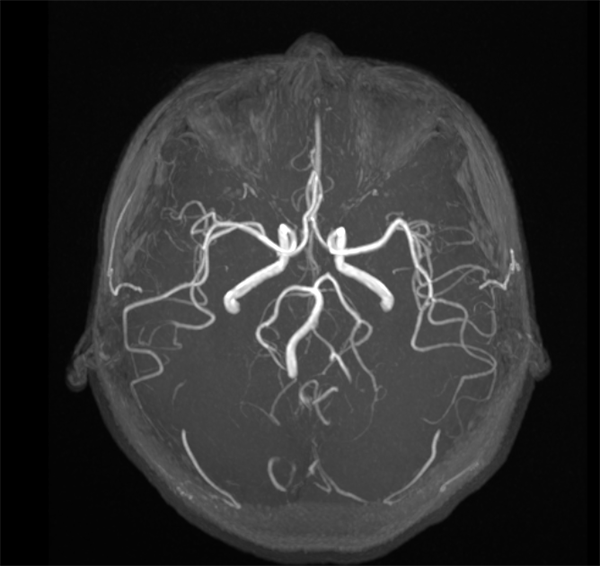

MRA即磁共振动脉血管成像。头颅MRA对颅脑和颈部的大血管显示效果好,可对颅内的血管有无狭窄、有无闭塞、有无血栓及出血性疾病,脑动脉瘤和脑血管畸形进行初步诊断和评估。